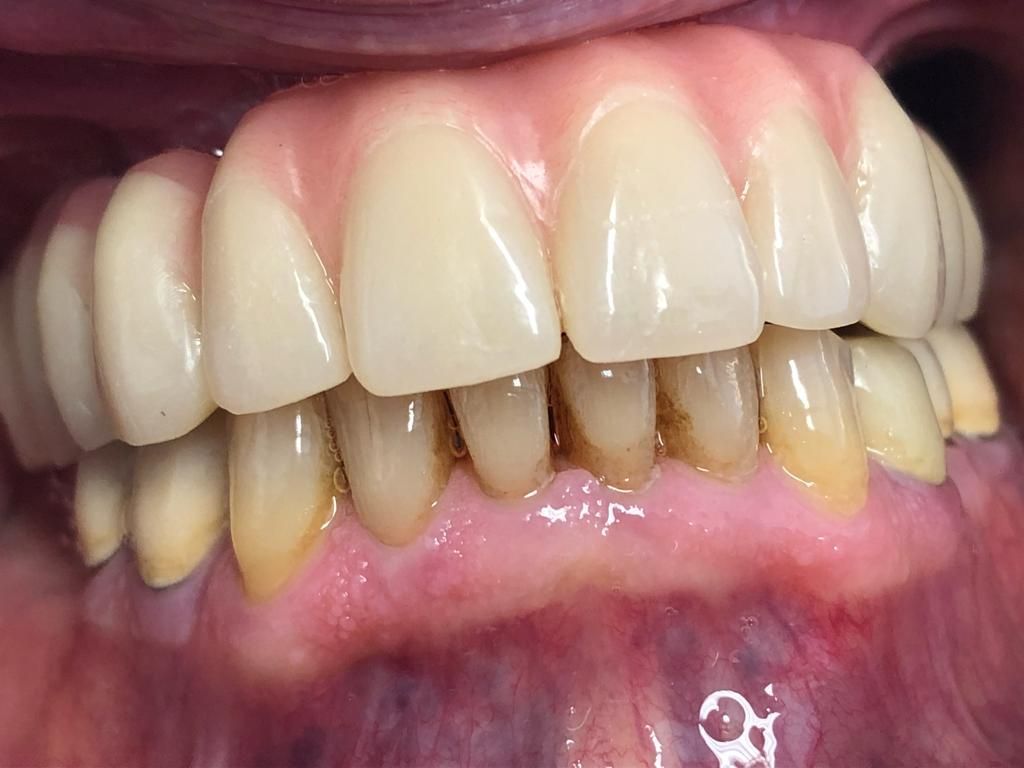

Aspetto

Naturale:

I denti supportati da impianti appaiono e funzionano come denti naturali, migliorando il tuo sorriso e la tua fiducia.